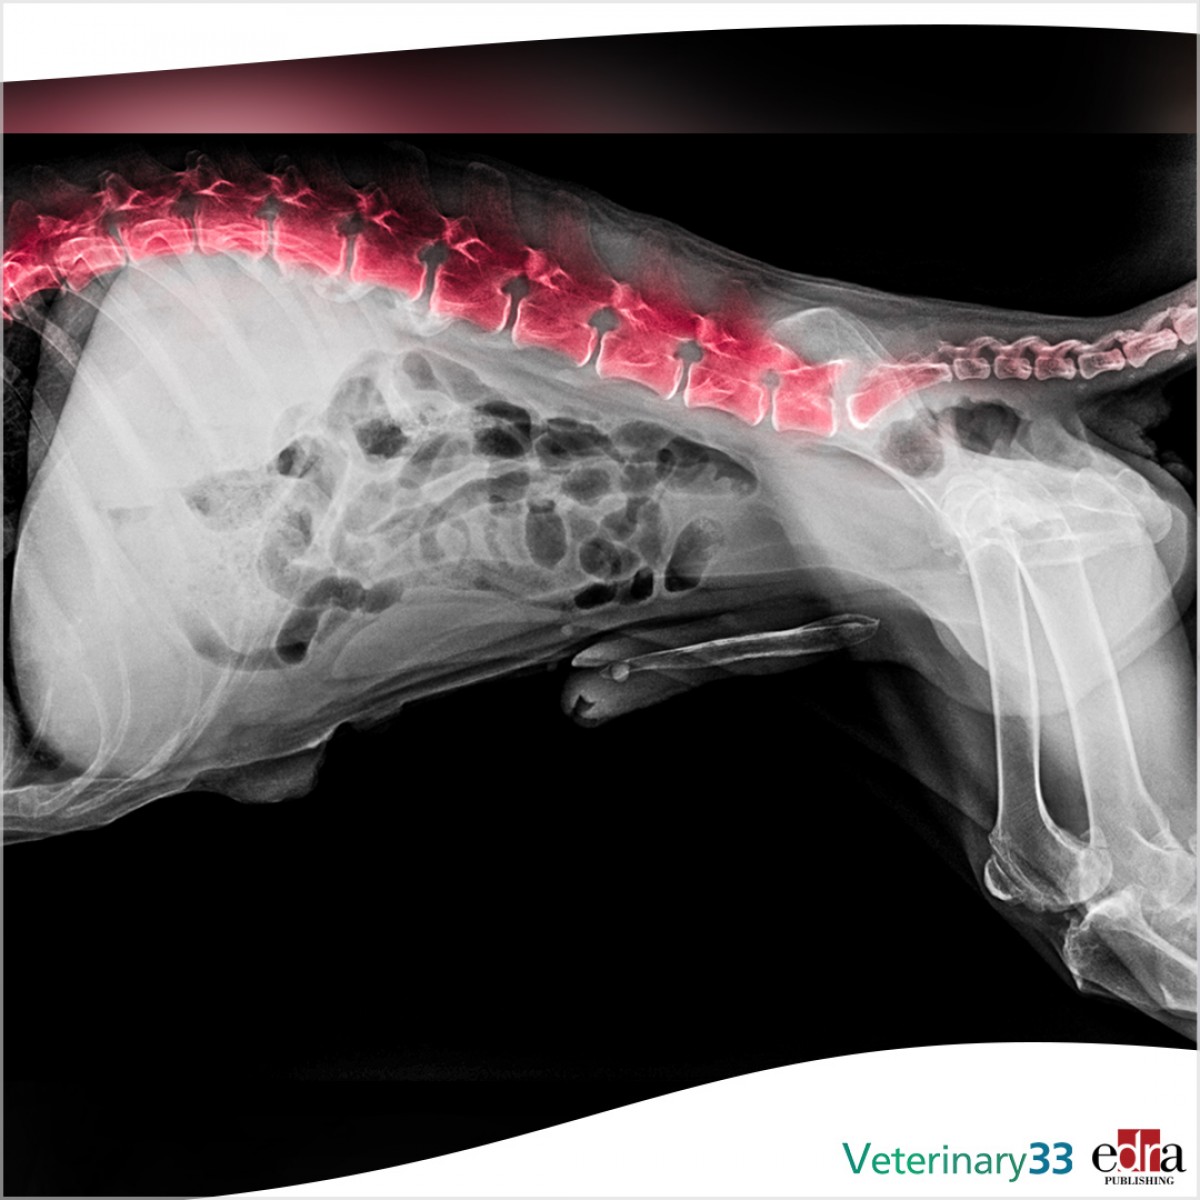

Clinical Presentation, Treatment, and Outcome in 41 Dogs With Spinal Epidural Empyema

There is limited information on canine spinal epidural empyema (SEE). The aim of this multicenter retrospective study is to describe the clinical presentation and outcome of dogs undergoing spinal surgery or conservative management for SEE. Forty-one dogs met the inclusion criteria; the SEE was treated surgically in 17 dogs and conservatively in 24 dogs.

Two dogs underwent spinal surgery after failure of conservative management, meaning that 19 dogs in total had spinal surgery. Long-term (i.e., >6 months) follow-up was available in 35 dogs (19 conservatively treated and 16 surgically treated dogs). Recovery to a functional pet status was achieved in 15/19 (78.9%) conservatively treated and 12/16 (75%) surgically treated dogs. There was no significant difference (p = 1.000) in long-term outcome between conservatively and surgically treated dogs (78.9 and 75%, respectively).

However, significantly more surgically treated dogs were non-ambulatory at presentation (9/17 vs. 5/24, p = 0.048) compared with conservatively treated dogs. This study suggests that conservative treatment may be appropriate for dogs with SEE that are ambulatory at presentation and that surgically treated dogs generally have good outcomes. Age may be a negative prognostic indicator as dogs with poor long-term outcomes were significantly older than dogs with a good long-term outcome (p = 0.048). A larger prospective randomized study may provide further insight on the treatment and outcome of SEE in dogs.

“Multicenter Study of Clinical Presentation, Treatment, and Outcome in 41 Dogs With Spinal Epidural Empyema”. Emma J Laws, et al. Front Vet Sci. 2022 Mar 7;9:813316.  doi: 10.3389/fvets.2022.813316.